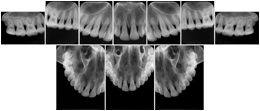

Intra-oral radiography typically involves acquisition of multiple images of various parts of the dentition. Many digital radiographic systems offer customized templates that are used for displaying the images in a study on the screen. These templates may also be referred to as mounts or view sets. The Structured Display Object represents a standard method of encoding and exchanging the layout and intended display of Structured Displays. A structured display object created in this manner could be stored with a study and exchanged with images to allow for complete reproduction of the original exam.

3. A dental provider wishes to capture a series of DICOM IO images for the patient’s dentition. The tooth morphology, teeth are divided into molars, premolars, canines and incisors, and a number of images for each jaw. The anatomic information was captured utilizing the triplet of schema. This standard code sequence is based on ISO 3950-2010, Dentistry - Designation system for teeth and areas of the oral cavity.

Every IO image should have anatomic information either through the primary or modifier sequence.

In most standard cases, images are oriented in structured layouts. These structured displays are useful to be shared between providers for reference purposes.

Table OO.1.1-1 shows structured display standard templates, where Viewset ID is based on the Japanese Society for Oral and Maxillofacial Radiology (JSOMR) classification provided by JIRA (Japan Medical Imaging and Radiological Systems Industries Association, www.jira-net.or.jp). Expected or typical teeth to be imaged location, region and designation codes are based on ISO 3950-2010, Dentistry - Designation system for teeth and areas of the oral cavity. For all the hanging protocols listed in OO.1.1-1, the value to use for Hanging Protocol Creator (0072,0008) is "JSOMR" and the value to use for Hanging Protocol Name (0072,0002) does not include "JSOMR" (e.g., "DL-S001A", not "JSOMR DL-S001A").